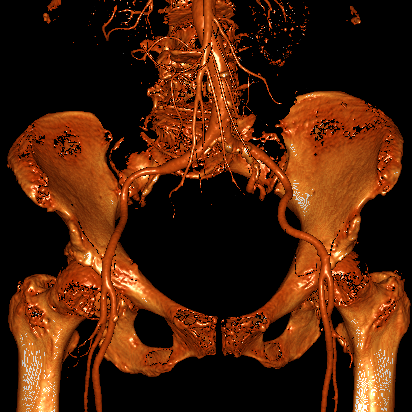

血管入路评估:双侧股动脉细小且分叉高,最窄处不到5mm,不满足可用TAVR器械对于股动脉入路最小径线的要求。患者锁骨下动脉、颈动脉同样细小,无法作为替代入路。患者升主动脉瘤样扩张,经升主动脉入路风险极高。

经TAVR团队谨慎分析、讨论后,认为本例患者升主动脉瘤样扩张、横位心,如采用自展式瓣膜进行TAVR,发生升主动脉损伤、瓣膜移位甚至瓣膜栓塞等严重并发症的风险高,采用球扩式瓣膜进行TAVR是更合理的选择。因患者外周动脉细小,经股动脉、经锁骨下动脉或经颈动脉TAVR均不可行,同时因升主动脉瘤样扩张,经升主动脉TAVR风险极高,而经腔静脉入路是可行的选择。因此,团队决定经由腔静脉至腹主动脉建立手术入路,并采用纽脉医疗球扩式Prizvalve经导管主动脉瓣系统实施TAVR。

患者术后恢复过程顺利,无严重并发症发生,术后CT示腹主动脉-下腔静脉瘘被完全封堵、未见明显腹膜后血肿,患者于术后一周康复出院。